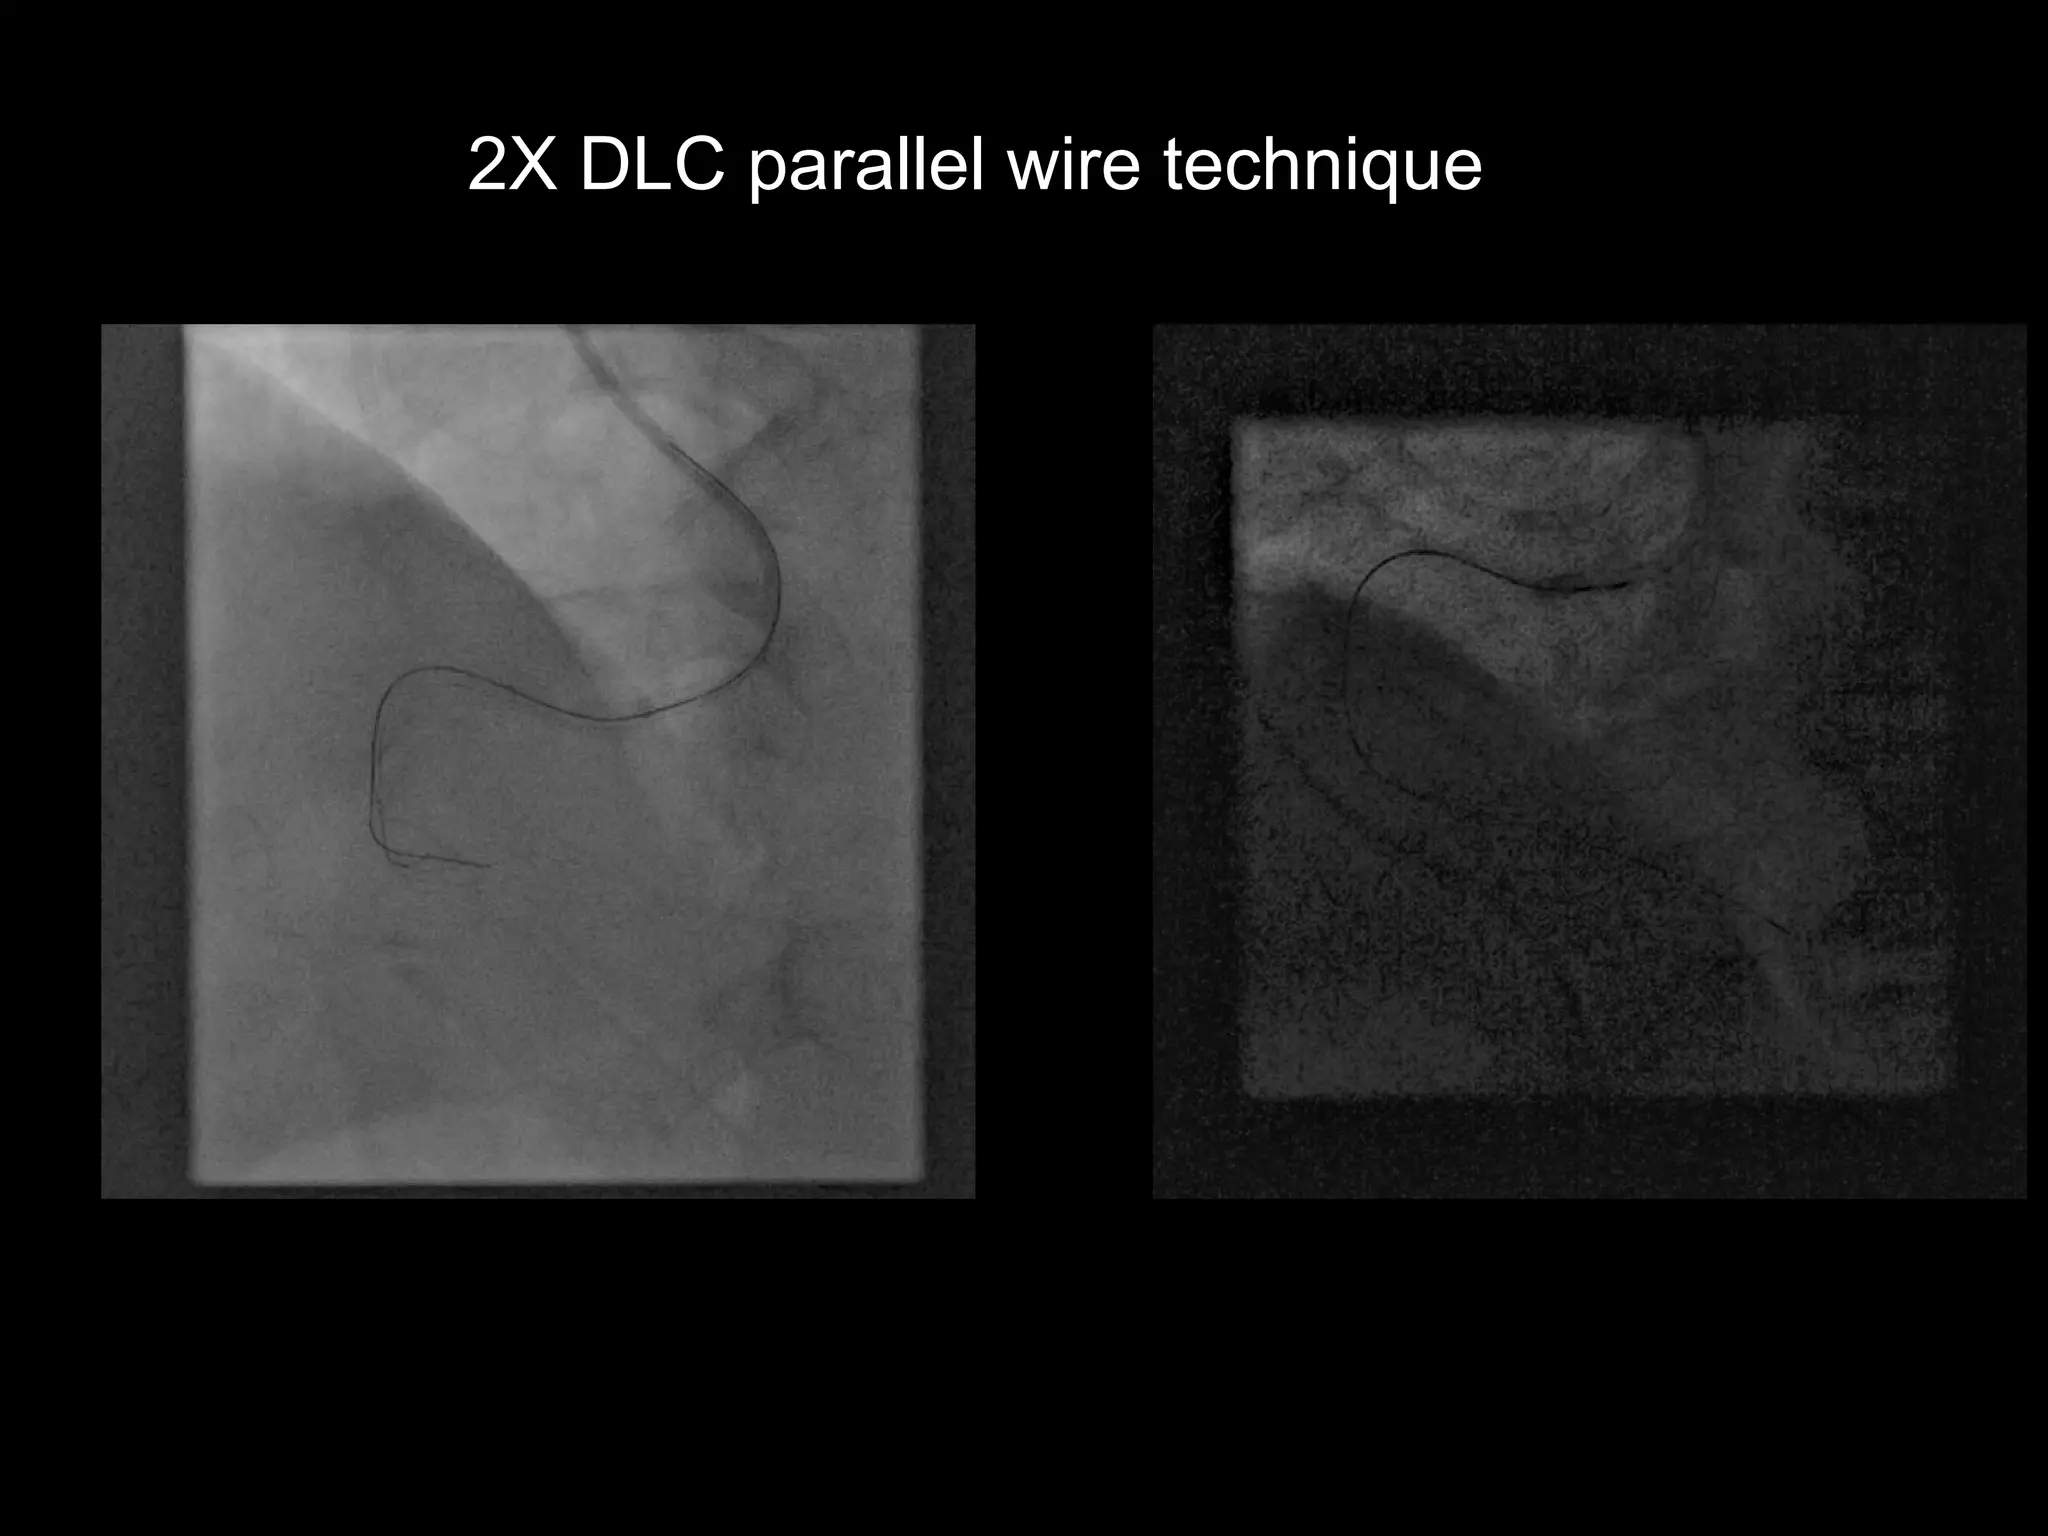

2X DLC parallel wire technique